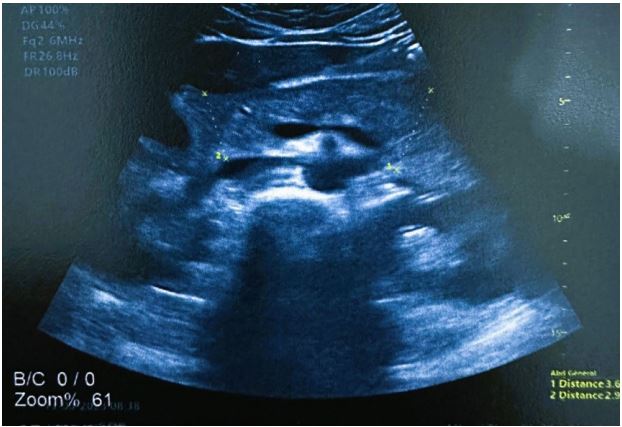

A Moroccan 17 year old male presented to the emergency department for four days of newly experienced epigastric pain associated to non-bloody and non-bilious emesis. The patient the child was diagnosed with epilepsy for which treatment with sodium valproate was initiated. The last dosage is changed nine months before from 750 mg to 1 g to maintain a dose of 20 mg/kg/d. There was no seizure the last year. On presentation he denied history of other new medications, supplements, alcohol or drug use, gallstones, fevers or chills. The epigastric pain was intense and resistant to anttispasmodic and oméprazole. Physical examination on arrival was notable for uncomfortable appearing, he complains of intense localized pain in the epigastrium radiating towards the back with an attitude of leaning forward. He was apyretic. On palpation we noted a focal epigastric tenderness with non-peritonitic abdomen. Respiratory and hemodynamic functions were stable. blood pressure 125/67, pulse 87, respiratory rate of 20, spo2 of 100%. The rest of the physical examination findings were unremarkable without any rashes, joint swelling, or adenopathy. Serum laboratory investigations in the emergency department revealed the following pertinent and significant findings: lipase level of 462 U/l, white blood cell count of 11.000 per mm3 , Activated protein C 27 mg/l, hemoglobin 10.6 g/dl, AST 28U/L, ALT 25U/L, Total bilirubin 8.2 mg/L, sodium 141 mmol/l, potassium 4.2 mmol/l, BUN 0.35 g/l, creatinine 10,2 mg/l, calcium 90 mg/l, and. All other initial laboratory invetigations within normal limits or insignificant. Patient was resuscitated with two liters of isotonic saline serum, received a total of 40 mg of intravenous omeprazole, 500 mg of intravenous paracetamol, and 4 mg of intravenous morphine. Initial abdominal ultrasound showed a normal gallbluddder, without any stones, gallbludder wall thickening, or common bile duct dilatation. the pancreas is globular with infiltration of gastric fat and presence of moderate peritoneal effusion (Figure 1). Subsequently, patient underwent a computed tomography of abdomen and pelvis with intravenous contrast (Figure 2). The pancreas was enlarged, had a homogeneous density, with a discreet homogeneous enhancement without an area of pancreatic parenchymal necrosis. presence of a peritoneal effusion of medium abundance surrounding the pancreas, perigastric, perihepatic, perisplenic level and in pelvic slope. The gallbladder, bile ducts, liver, spleen and kidneys were without abnormalities. The appearance was an acute edematous pancreatitis grade E of Balthazar. Patient was admitted to intensive care unit, he continued to receive intravenous boluses and maintenance fluids per standards of care for acute pancreatitis, along with adjunct therapies including antispasmodic, omeprazole and morphine to control pain. Food is reintroduced gradually from the 3rd day after the nausea and vomiting have disappeared and the pain has been controlled. we started with water, herbal teas, vegetable broths in small volumes. All this while monitoring digestive tolerance and the absence of pain. During the first days of hospitalization, patient underwent an extensive panel of investigations including bili-MRI showed the absence of stones in the Wirsung duct and bile ducts which are not dilated, no malformation or pancreatic mass is revealed (Figure 3). The other investigations were hematological toxicology screen, viral screening (including A, B and C hepatitis panel, respiratory viral panel, measles mumps rubella panel Epstein barr, cytomegalovirus panel), TPHA VDRL serology, tuberculosis quantiferon, lipid panel (cholesterol 1.46 g/L, triglycerids 0.9 g/L), blood smear, thyroid panel, antinuclear and anticardiolipin antibodies, hemoglobin electrophoresis; all returning either within normal or unremarkable limits. The absence of another cause responsible for pancreatitis led us to consider the drug etiology, particularly sodium valproate. Neurology consult was placed. Treatment with valproate of sodium was stopped and replaced by levetiracetam 250 mg twice a day. The opatient made a full recovery and was discharged after a total of eight days with prescription of levetiracetam. Any epileptic crisis was observed. The patient continue to have regular outpatient neurology follow up.

Figure 3: Bili-MRI showing absence of biliar storage in gallbludder, bile ducts and wirsung duct, and no malformation or pancreatic mass was revealed.